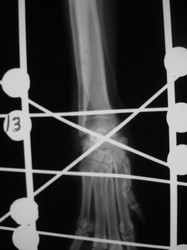

PRÁCTICAS CURSO DE FIJACIÓN EXTERNA PERFECCIONAMIENTO.

Artrodesis carpo.